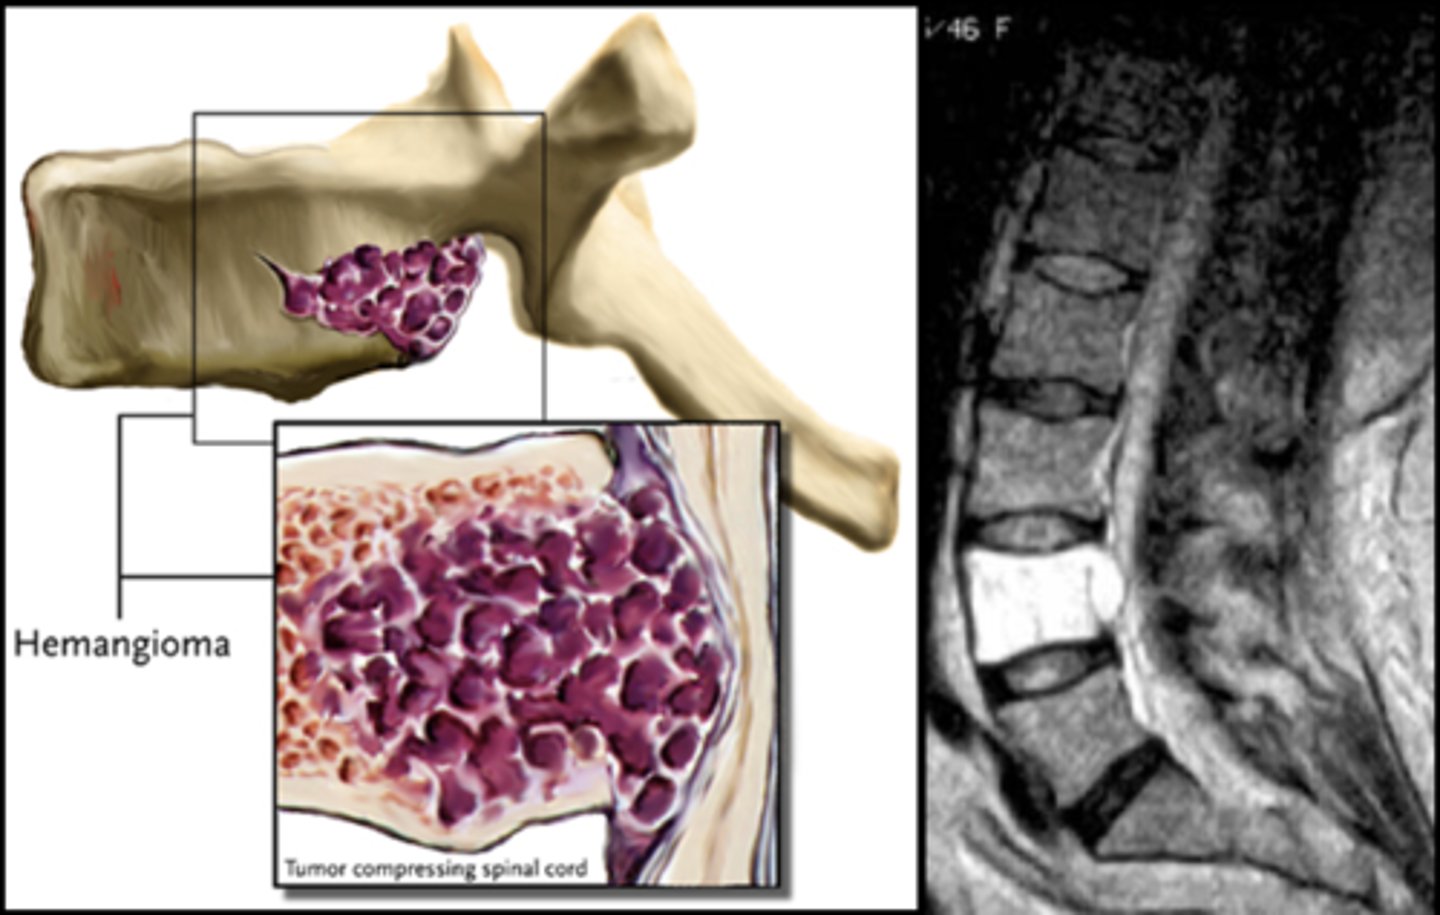

- Vertical striations (corduroy cloth)

- Expansion (rare) may result in neurologic findings

- Skull ("sand dollar")

- Paravertebral swelling

State the radiographic features of vertebral hemangioma

Expansile

_____ vertebral hemangioma

- Left: Paget Disease

- Middle: Vertebral hemangioma

- Right: Osteoporosis

Complete the DDx for vertebral hemangioma